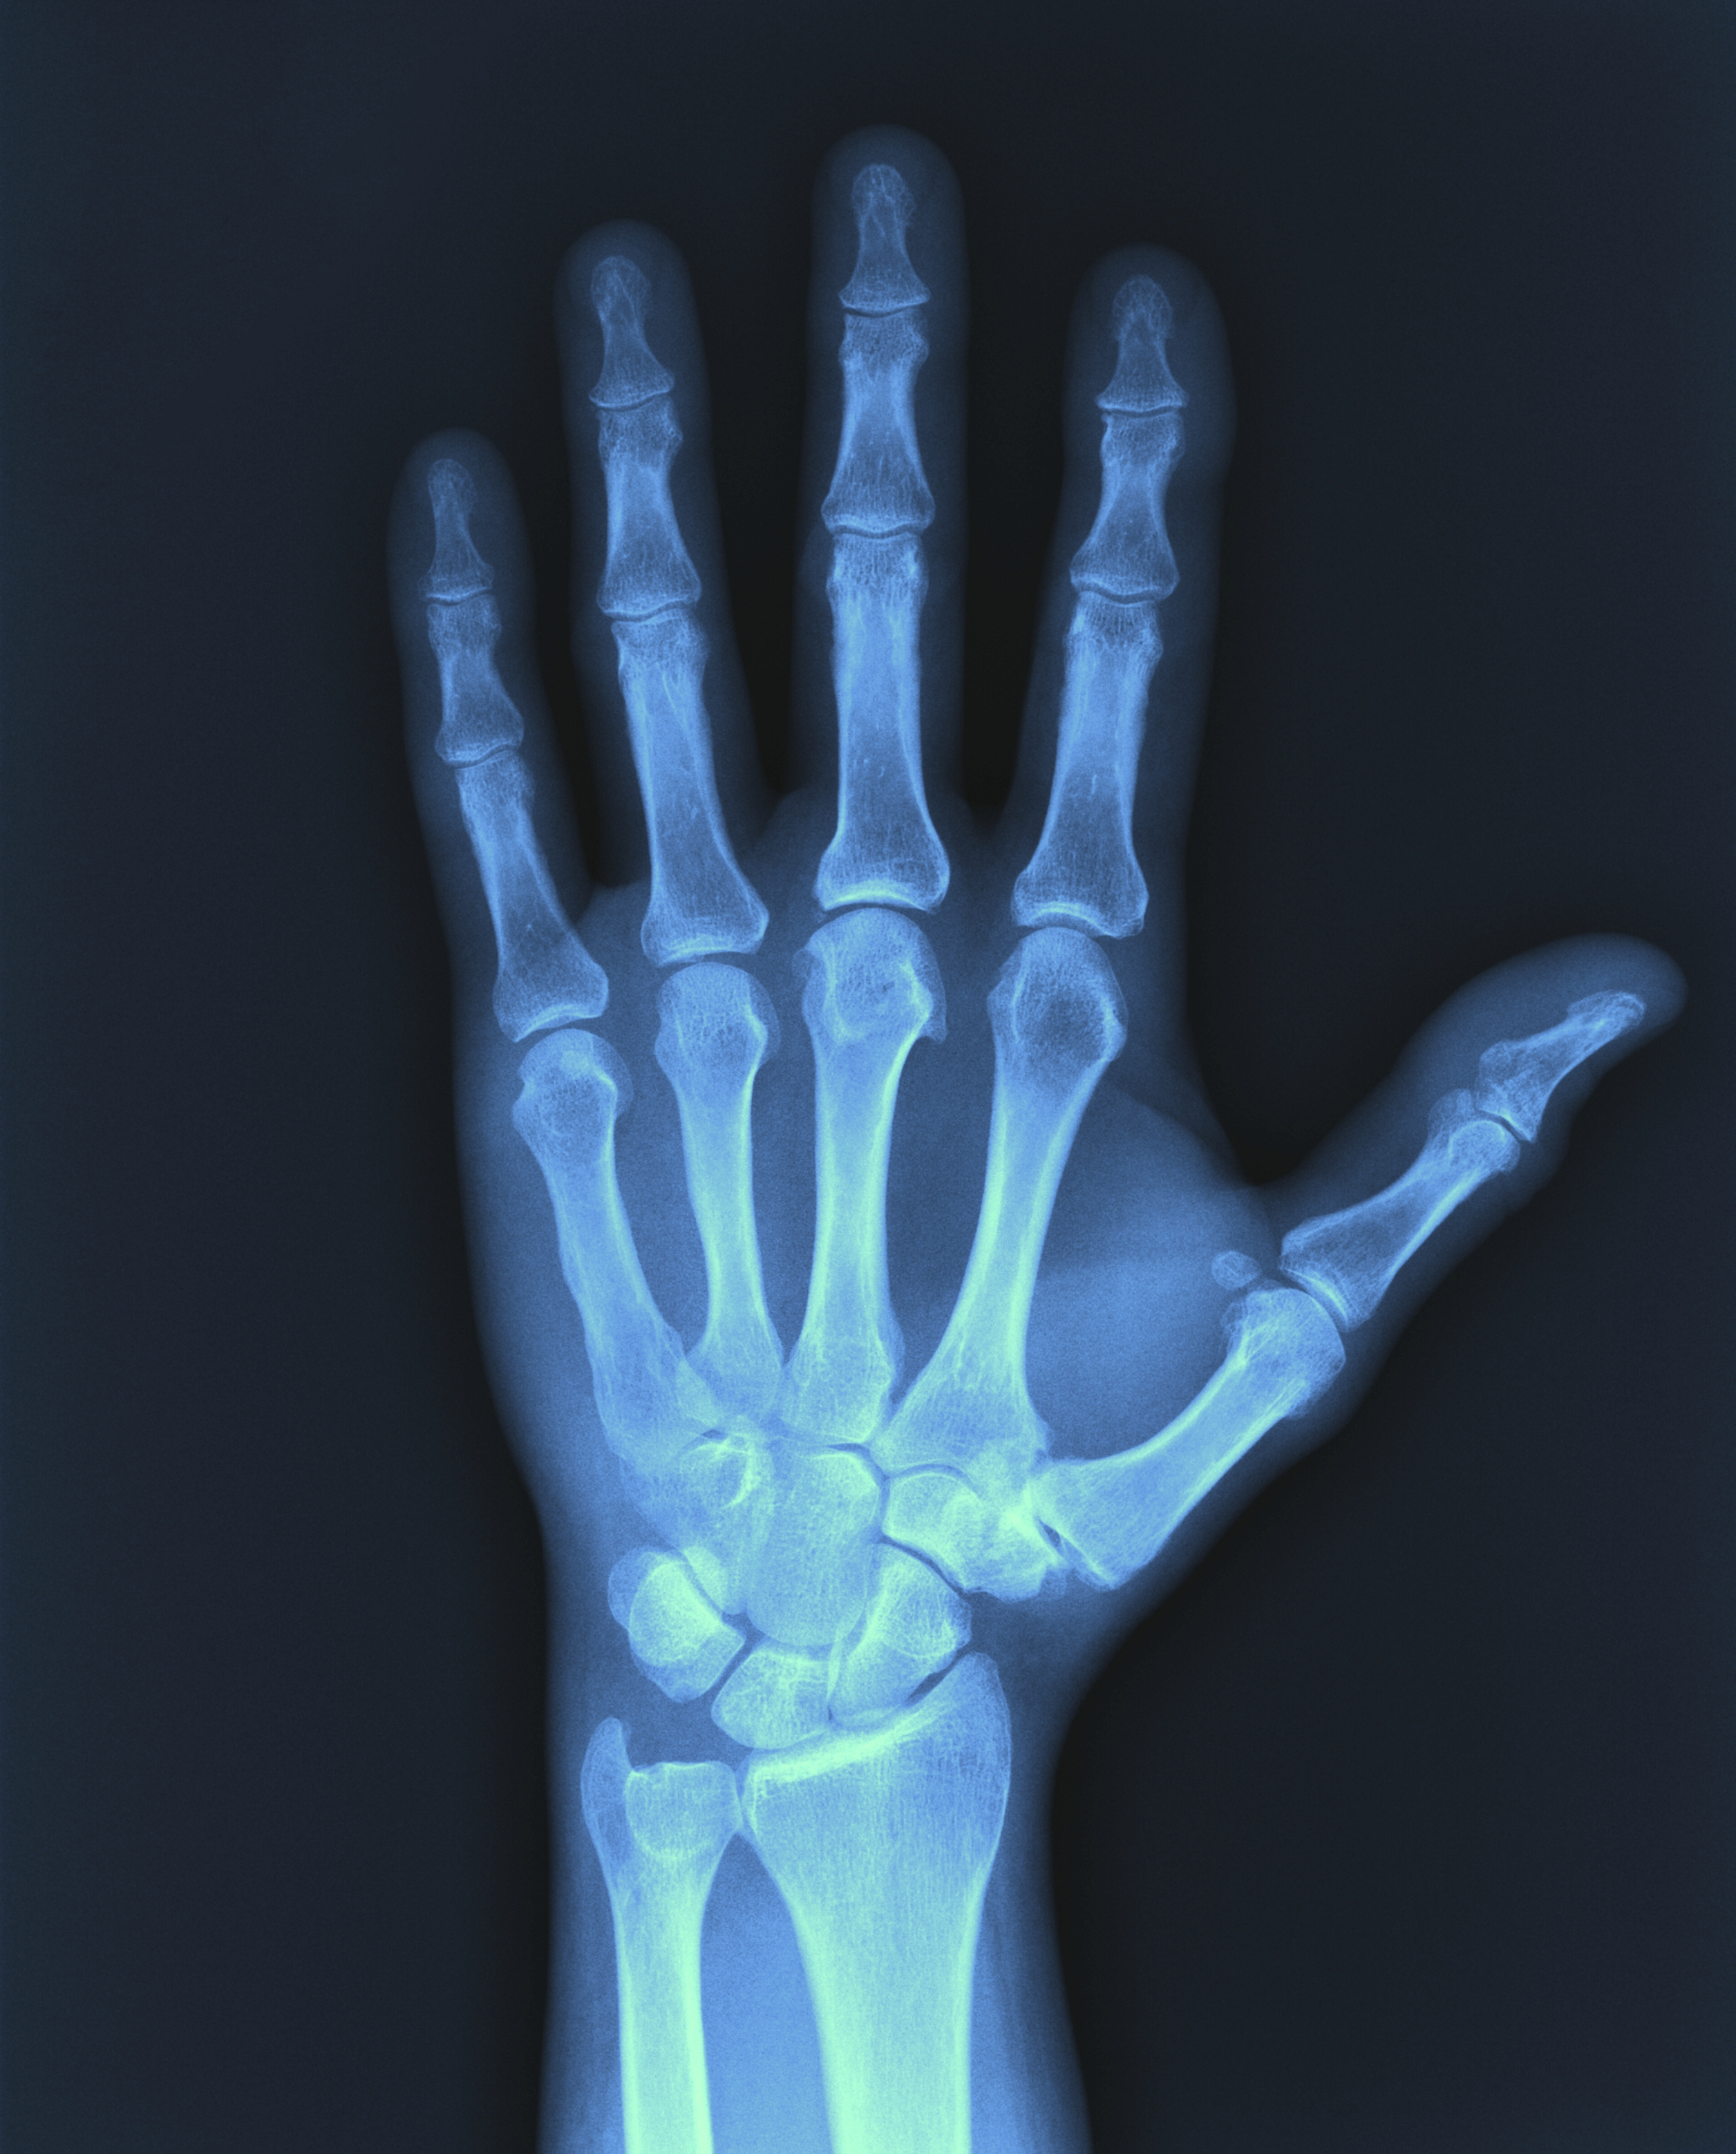

The Norwegian Directorate of Immigration (UDI) informs us on its website that if there is doubt as to the age of a young asylum seeker, it may request his/her consent to carry out an age assessment. This 'consists of two parts; an X-ray of your hand and of your teeth. A doctor will look at these X-rays and evaluate your correct age. If you do not wish to undergo such an examination, it can have a bearing on whether your asylum application will be granted or rejected.' (1).

In September 2010, the Norwegian Medical Association made the decision to recommend that 'doctors ought not to participate in the age assessment of unaccompanied minor asylum seekers based on an x-ray of the hand and wrist (…) The central board recognises that the authorities have a legitimate need to clarify which asylum seekers have the rights afforded to children and which are adults and therefore have different and fewer rights. In different contexts, doctors fulfil the role of therapist as well as that of expert and are thereby subject to different rules. Nevertheless, the central board's opinion that doctors should not participate in age testing of unaccompanied minors is based particularly on the inaccuracy of the methods and the extent to which consent is informed and voluntary' (2).

The complaints put forward point out that the Directorate of Immigration has used age determination extensively despite disagreement in the medical profession, and that while it was initially used only in cases of doubt, it is now performed on almost all asylum seekers who purport to be under the age of 18 years (4). The complaints refer to the fact that the Norwegian Medical Association has advised its members against participating in x-ray examinations with a view to determining the age of unaccompanied refugee minors, and question whether the activity of the doctor concerned contravenes the Code of Ethics of the Norwegian Medical Association.

Based on the Code of Ethics for Doctors, chapter I, sections 1, 2 and 9 (8), as well as chapter IV, section 3 (box 1), the Medical Ethics Council stated: 'The Council concluded that the doctor who was the subject of the complaint performs a very particular expert role for the Directorate of Immigration, that there is no medical indication for the examinations, and that the method used is disputed. Age assessment by means of x-ray of the hand and wrist and dental examination requires valid consent, i.e. that the consent is given on an informed basis by a person with the capacity to give that consent. There is reason to question whether voluntary, informed consent is possible to achieve for these examinations. As the Norwegian Medical Association states, according to the Directorate of Immigration an individual's refusal to permit his/her age to be assessed may have consequences for the asylum application. This is first and foremost a rights issue for the person being examined, but it may also be problematic for the healthcare personnel undertaking the examinations.

The Medical Ethics Council finds that by performing age testing of unaccompanied minor asylum seekers based on inaccurate methods which he himself states 'are not as reliable as might be desired', and with no possibility of ensuring valid consent, the doctor who is the subject of the complaint has contravened the Code of Ethics for Doctors, chapter I, sections 2 and 9. The Council furthermore believes that he has made expert statements which in the opinion of the Council are not based on 'examinations that are sufficiently extensive for the purpose', cf. chapter IV section 3'. The case is reported in the Medical Ethics Council's 2016 Annual Report (9).

The doctor who was the subject of the complaint withdrew 'following a general assessment' in December 2016 (10), and the Norwegian Institute of Public Health was given national responsibility for evaluating and improving the methods (transferred to the Department of Forensic Medicine, Oslo University Hospital on 1 January 2017) (11). They reported that current age testing is not sufficiently based on science, and that therefore they cannot take professional responsibility or continue the practice (12). In collaboration with the Norwegian Knowledge Centre for the Health Services, Norwegian Institute of Public Health, the expert group for forensic medicine has conducted a systematic survey of the scientific basis for several methods used for medical age assessments (13, 14).

Pending new methods, the Directorate of Immigration is assessing hand and wrist x-rays itself (15). In June 2017, the Department of Forensic Medicine, Oslo University Hospital launched the Bioalder instrument (16, 17). This method produces an interval estimate for age with a probability of 75 % and 95 % respectively, based on different methods for determining age (18, 19).

We understand that these methods are based on dental images and images of the hand/wrist. These are interpreted by a dentist and radiologist respectively, and the result can then be entered into the Bioalder instrument by case officers in the Directorate of Immigration. The report that is generated is used in processing the case further.